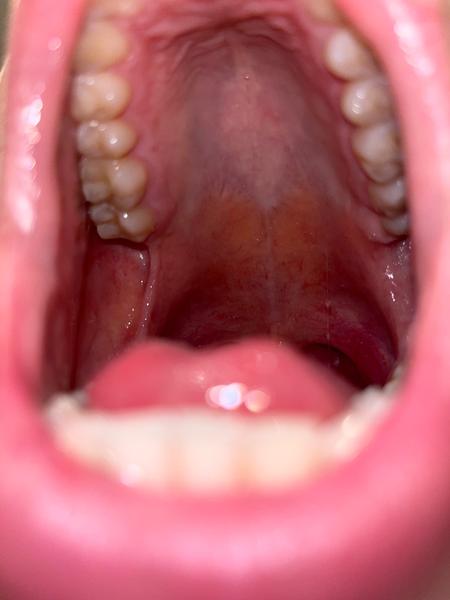

už včera jsem se cítil slabý a dnes je to podobné. Mám trochu povléklý jazyk, ale v krku mě nebolí ani jiné příznaky nemám. Žádná teplota ani rýma. Ráno jsem viděl na mandlích bělavý pupen nikoliv čep, ale ten zmizel. Jednou jsem ho už tam měl a byly to ucpané slinné žlázy. Kromě povlaku v puse a slabosti nemám jiné příznaky. Dokonce tepovou frekvenci mám nízkou. Kolem 50 t/min (jsem sportovec).

na mandlích, ani na jazyku slinné žlázy nejsou přítomny, proto těžko říct, co za pupen mohlo na mandli být. Pokud nepociťujete na mandlích či v dutině ústní bolest a celkově se cítíte dobře, pak bych tomu nevěnovala větší pozornost. Povlak na jazyku je ovlivněn též stravou či léky a může rychle zmizet. Na mandli mohou být zbytky jídla, které po polknutí zmizí.

Kdyby se objevily příznaky jako horečka, bolest v krku nebo bolest v dutině ústní, doporučuji navštívit Vašeho PLDD k dovyšetření.